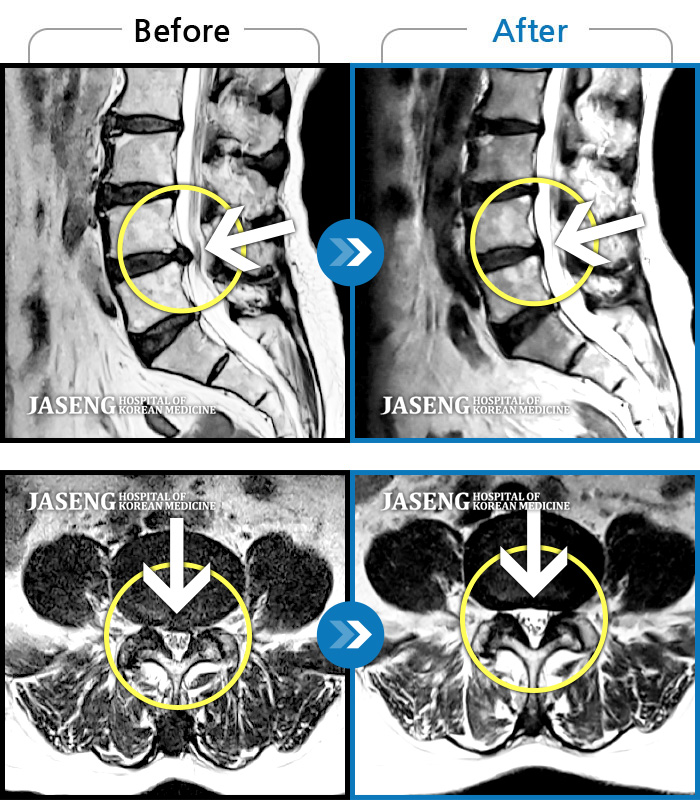

처음 내원 시 허리와 좌측 골반이 많이 아프고, 좌측 다리로 저림과 감각 저하가 있어서 보행이 원활하지 못했으며, 야간통으로 잠도 못 자고 통증 심하여 정상적인 활동이 힘든 상태셨습니다.

2023.09.16 ~ 2024.09.24